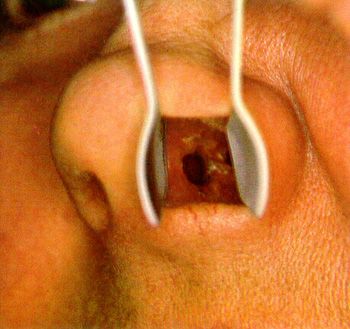

nejm:不容忽视的鼻中隔血肿

图片尺寸640x480